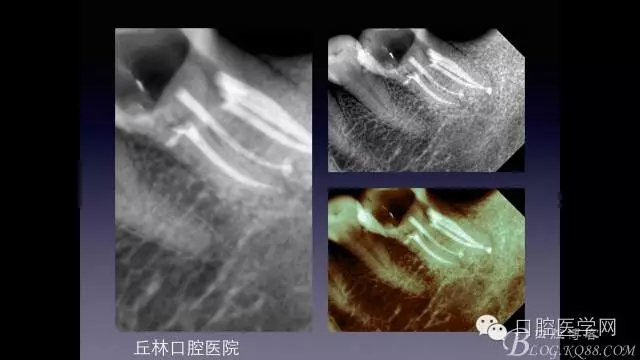

一例36根管再治療,五個根管冷側加壓病例